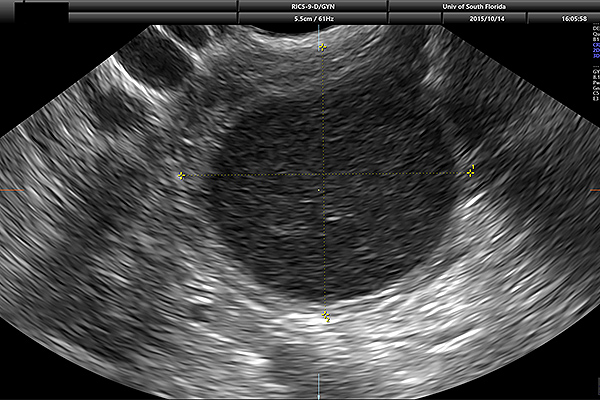

Transvaginal ultrasound is a diagnostic tool used to examine your reproductive organs (uterus, fallopian tube, ovaries, cervix and vagina). Using 2D and 3D transvaginal ultrasound imaging, our skilled ultrasound experts can identify a range of conditions and causes of symptoms, including:

Through our Obstetrics and Gynecology department, USF Health offers ultrasound for a variety of diagnostic reasons.

An ultrasound is the first time you see your little one. With both 3-D and 4-D ultrasound capability, our skilled technicians at USF Health evaluate your baby’s health and development. They can also screen for major congenital anomalies as well as estimate the gestational age of fetuses.